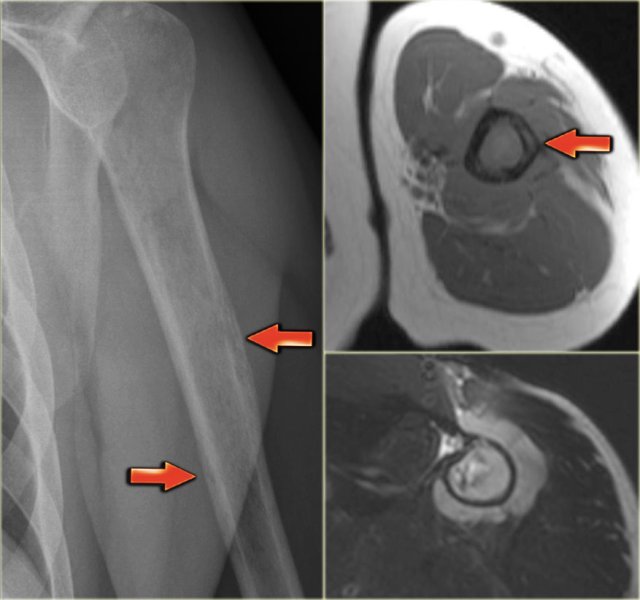

The plain radiograph on the left shows an ill-defined lytic lesion of the humerus diaphysis.

Notice tunneling of the cortical bone (red arrows).

On the MR notice the linear abnormalities within the cortical bone and the circumferential soft tissue mass.

Differential diagnosis (depending on age): Ewing's sarcoma, osteomyelitis and bone lymphoma.

Biopsy revealed Non-Hodgkin lymphoma